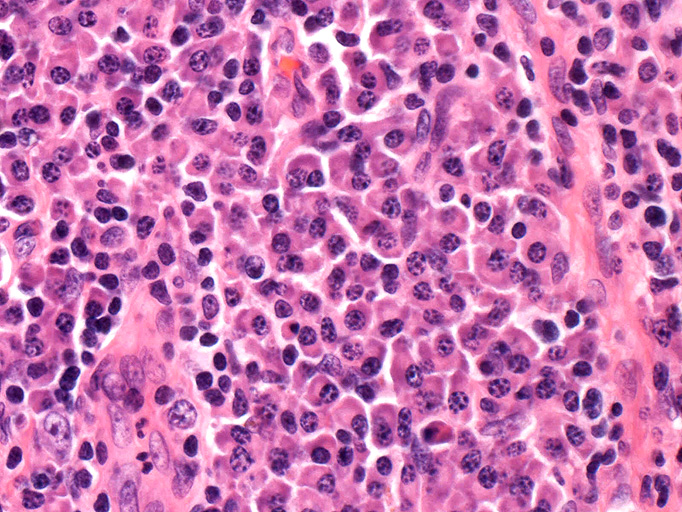

2. 形質細胞型 plasma cell type(PC型):増加を示す濾胞間にびまん性密に多クローン性形質細胞浸潤が認められる。

形質細胞型 plasma cell type

- 肉眼所見では3-15cmで数個の独立した結節からなる病変。小さな周囲リンパ節を伴うこともある。

- HV型と異なり種々の症状や異常検査値を示す

これらの異常は胚中心細胞の産生するIL-6のためと考えられている。患者さんの血清IL-6は高値のことが多く, 抗IL-6抗体が検出の報告もある。